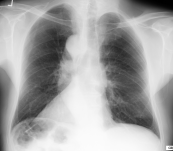

翻转

- 从 变换 下拉菜单中选择 水平翻转,或按 Ctrl + Shift + [,水平翻转图像

- 从 变换 下拉菜单中选择 垂直翻转,或按 Ctrl + Shift + ],垂直翻转图像